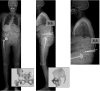

Introduction: The role of the pelvic area in sagittal balance is evident for spinal surgeons, but the influence of the coxofemoral joint is underestimated and inadequately explained by conventional imagery. Comprehensive analysis of the pelvic and subpelvic sectors as part of the sagittal, frontal and cross-sectional balance of the trunk sheds new light on some spinal diseases and their relation to the pelvis.

Results: Disturbances can come from atypical morphotypes or from unusual postures as in aging spine. The measurement of available extension and the concept of available flexion provide new information regarding individual's adaptation to the imbalance induced by disorders of the spine or lower limbs.

Conclusion: A comprehensive assessment of each patient and in particular of the complex comprising the spine and the pelvis, is essential for understanding each individual's adaptation to the imbalance induced by disorders of the spine or lower limbs.